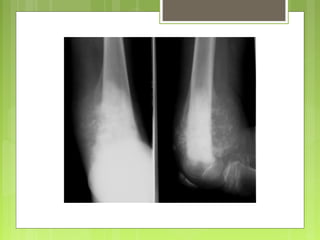

Signos de malignidad

 Zonas líticas

 Reacción perióstica

 Efracción de la cortical

 Imagen de osificaciones de partes blandas

Osteosarcomas

Condrosarcoma periférico

 Invasión inmediata de partes blandas

 Difícil de visualizar en la radiografía

• Signos de malignidad

Atención a las formas debutantes :

 pequeña zona difusa

 pequeña reacción perióstica

enfrente de una zona densa